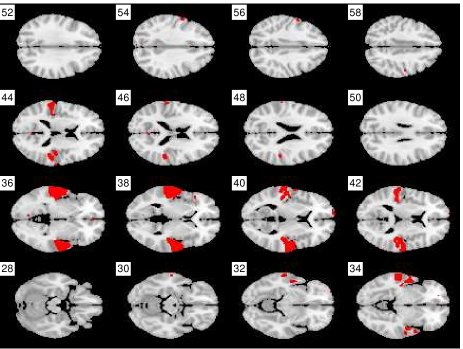

Figure 5 illustrates the kind of spatial maps that are found in the dense cluster. Dark areas along the lateral sides is used to highlight those voxels whose values differed more than three standard deviations from the mean. The numbers marking the slices are their Z-coordinates. The corresponding low-dimensional point is in Figure 2 numbered as 3. It is now possible to inspect the clusters more closely with domain experts.